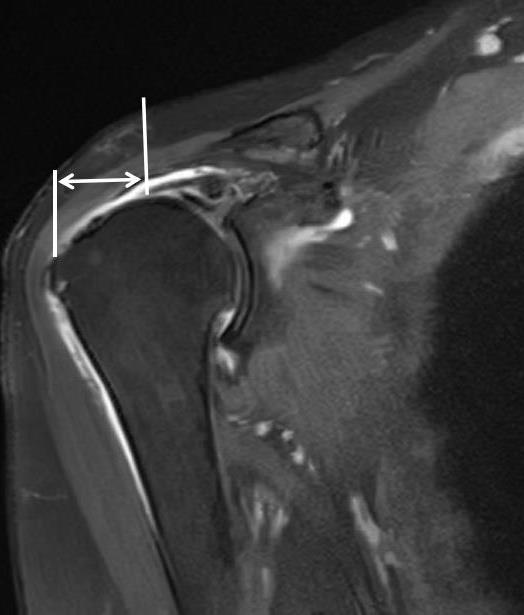

• 术前磁共振成像指标对肩袖全层撕裂患者行关节镜下肩袖修补手术后疗效的预测价值分析

2025, 31(9):9-16. DOI: 10.12235/E20250268

摘要 (134) HTML (152) PDF 1.69 M (108) 评论 (0) 收藏

摘要:目的 分析术前磁共振成像(MRI)指标对肩袖全层撕裂(FTRCT)患者行关节镜下肩袖修补手术(ARCR)后疗效的预测价值。方法 选择2020年1月-2023年12月该院收治的451例FTRCT患者,均接受ARCR治疗,回顾性分析患者的临床资料,随访1年,依据上肢功能障碍评定量表(DASH)评分,将患者分为肩关节功能改善组(n = 415)与肩关节功能未改善组(n = 36)。比较两组患者术前MRI指标和临床指标,采用多因素Logistic回归模型,分析FTRCT患者行ARCR后疗效的影响因素,绘制受试者操作特征曲线(ROC curve),分析术前MRI指标单独检测及联合检测,对FTRCT患者行ARCR后疗效的预测价值。结果 451例行ARCR的FTRCT患者,术后随访1年分析其疗效,肩关节功能未改善发生率为7.98%。与肩关节功能改善组比较,肩关节功能未改善组术前肌腱撕裂宽度和肌腱回缩距离更长,肌腱退变程度更高,肩峰肱骨间隙更短(P < 0.05)。相较于肩关节功能改善组,肩关节功能未改善组年龄更大(P < 0.05)。多因素Logistic回归分析结果显示,肩峰肱骨间隙 ≤ 7.15 mm(OR^ = 2.20895%CI:1.255~3.883)、肌腱退变程度2级至3级(OR^ = 1.81795%CI:1.066~3.096)、肌腱撕裂宽度 > 2.16 cm(OR^ = 2.24695%CI:1.242~4.059)和肌腱回缩距离 > 2.10 cm(OR^ = 2.18695%CI:1.311~3.646)为FTRCT患者行ARCR后肩关节功能未改善的危险因素(P < 0.05)。将肩关节功能未改善纳入阳性,肩关节功能改善纳入阴性,绘制ROC curve,分析术前MRI指标联合检测对FTRCT患者行ARCR后疗效的预测价值,曲线下面积(AUC)为0.903,敏感度为86.11%,特异度为87.47%。结论 FTRCT患者行ARCR后疗效较好,肌腱撕裂宽度 > 2.16 cm、肌腱回缩距离 > 2.10 cm、肌腱退变程度2级至3级和肩峰肱骨间隙 ≤ 7.15 mm为其疗效不良的危险因素,术前MRI指标联合检测的预测价值较高。